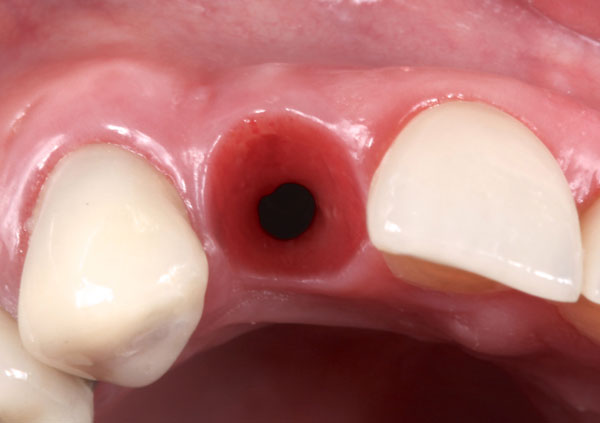

Immediately loaded implants in compromised sockets

Single-tooth replacement in the esthetic zone has been one of the most common indications for dental implant placement. Compromised teeth are removed using atraumatic principles and immediately replaced by an implant-supported provisional restoration, with excellent esthetic, biological, and functional results.

However, in cases of compromised sites with bone loss/gingival recessions, the clinical scenario presents a different dilemma. Until now, all developed surgical recommendations required long-term treatment with possible undesirable complications in the tissue architecture.

The Immediate Dentoalveolar Restoration (IDR) is a surgical and prosthetical technique established to broaden indications for immediate loading on individual teeth. In this way, tissue losses with varied extensions are reconstructed in the same surgical session of implant placement and provisional crown installation, reducing the number of interventions and keeping predictability on esthetic aspects. The IDR protocol was developed more than 12 years ago from the need to minimize the treatment time

In the course we discuss the scientific basis, the step-by-step technique, indications and bone biology. The IDR technique, which advocates minimally invasive surgery, flapless procedures, is presented as a viable and reproducible alternative.

It is presented several cases, which showed one or more compromised socket walls of the tooth involved, with or without changes of the gingival margin, some with more than 12 years of clinical, radiographic and CT scan follow-up.